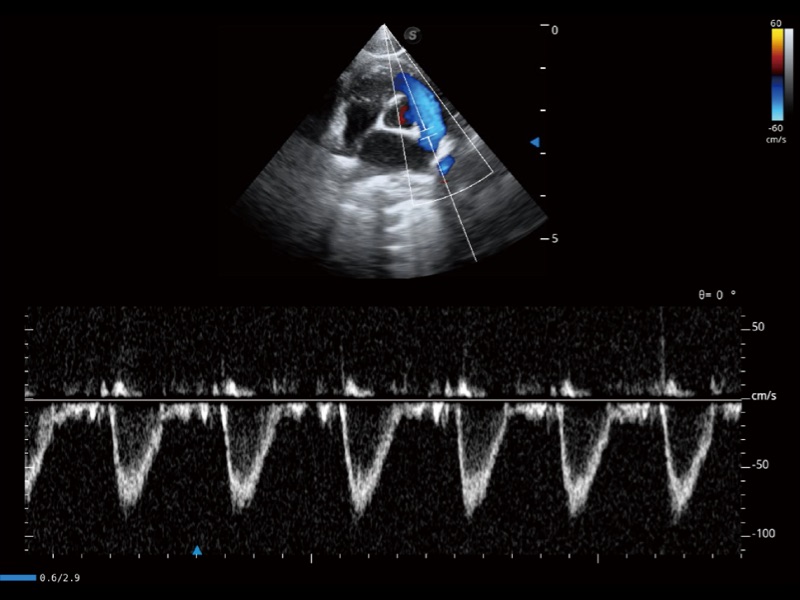

通过360度任意调节3条M型取样线,在同一心动周期上观察心脏不同位置的运动曲线,得到准确的心功能测量数据,有效评估心肌运动及左心室功能。

能够基于左心室壁追踪和辛普森法,自动计算射血分数,支持多个可移动点描迹,与手动测量相比,极大节省了动物医生的时间和精力。